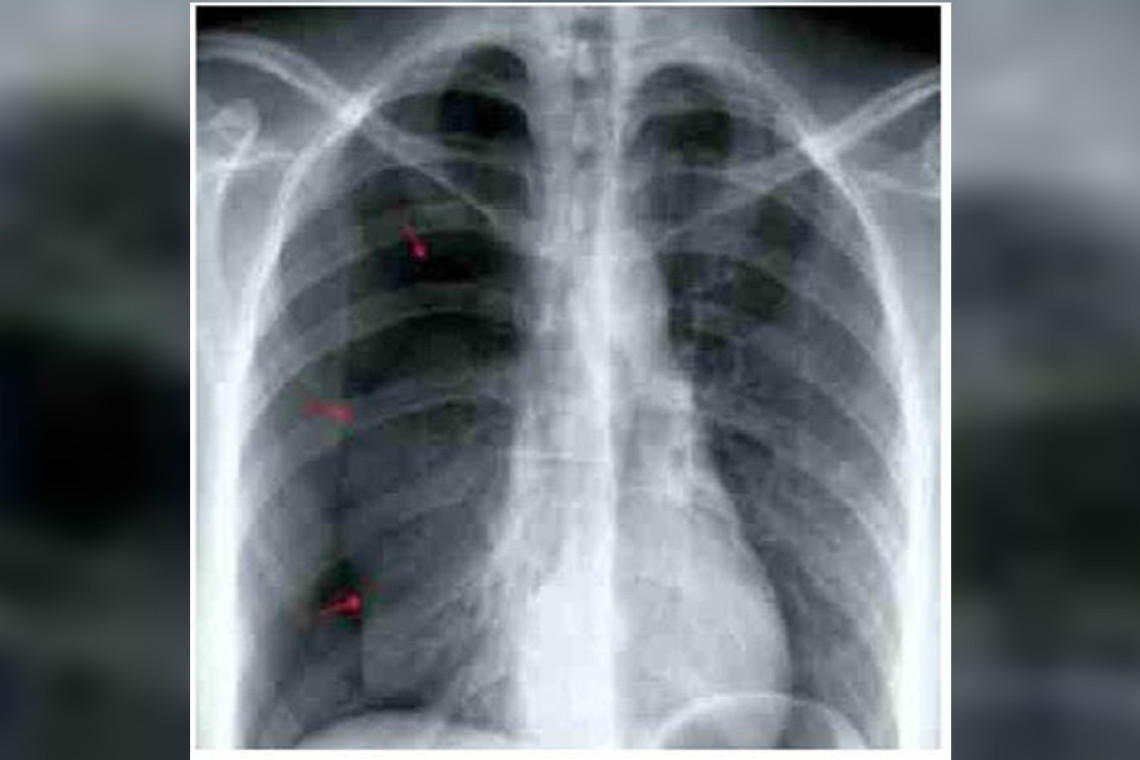

รอบนี้มาด้วยเหนื่อย+เจ็บอกขวาขึ้นมาทันทีทันใด ออกแรงหรือหายใจเข้าแล้วเจ็บมากขึ้น แพทย์ทำเอ็กซเรย์ดังภาพ พบปอดขวาแฟ่บลง (ลูกศรสีแดงคือแนวขอบของปอดที่หดลงมา)

บ่งบอกว่ามีภาวะปอดทะลุ (Pneumothorax) เกิดทางเชื่อมระหว่างโพรงอากาศในปอด กับช่องเยื่อหุ้มปอด (Pleural cavity) ลมได้เข้าไปยังช่องเยื่อหุ้มปอด ทำให้ปอดสูญเสียในการสร้างความดันในขยายปอด